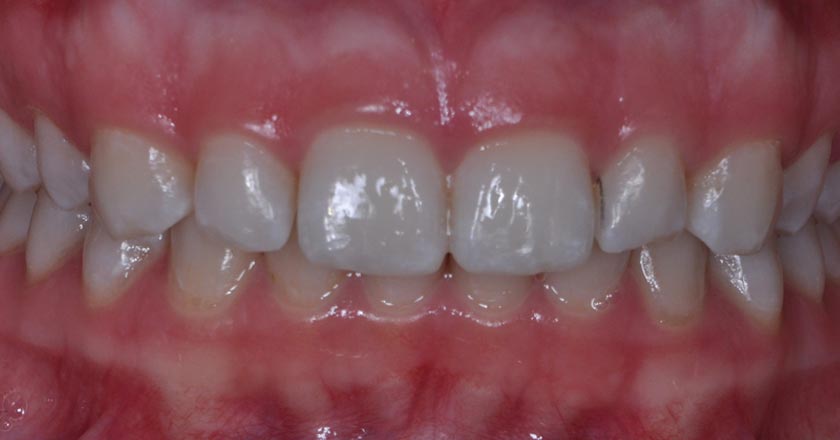

Gum Graft Upper - Before And After

Gum graft upper – before treatment